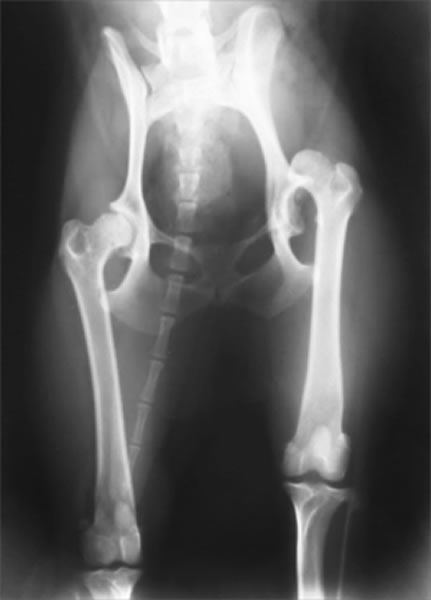

股関節形成不全症とは

成長過程で股関節(寛骨と大腿骨)の発育異常が生じ、股関節に緩みが引き起こされる疾患です。緩みのある不安定な股関節を動かすことで、関節の軟骨部分が損傷を受け関節炎がはじまります。関節炎による痛みから跛行を呈します。

好発犬種

ラブラドール、ゴールデン、バーニーズ、シェパード、ニューファンなどの大型~超大型犬で多い。柴犬、ポメラニアン、トイプードルなどの中型、小型犬でも起こります。

診断

触診、レントゲン検査

全股関節置換術は股関節形成不全やその他の股関節の異常(レッグペルテス、骨頭骨折等)に対して行われる根治的治療法で、機能の回復に関しては現在のところ最もすぐれた治療法です。機能しない、あるいは痛みを持つ股関節をチタンの人工関節に取り替える方法です。6カ月齢からあらゆる年齢で可能な手術です。

DPO(Double Pelvic Osteotomy)/ 二点骨盤骨切り術

TPO(Triple Pelvic Osteotomy)/ 三点骨盤骨切り術

5カ月齢~8カ月齢までの症例で有効な手術。腸骨・恥骨の二点もしくは腸骨・恥骨・坐骨の三点に骨切りをおこない、寛骨臼による大腿骨頭のカバーがよくなるよう腸骨を外側へ回転させる術式です